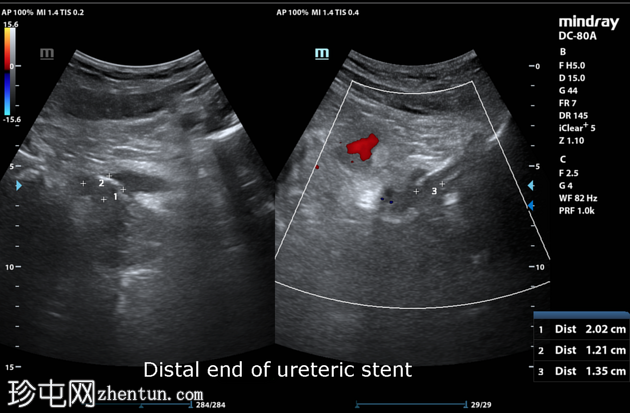

超声检查

右肾

右肾下极可见一结石,大小为0.9 x 0.6 x 0.9 cm(前后径 x 宽度 x 头尾径)。右肾轻度积水。右侧输尿管被肠道气体遮挡。输尿管支架近端位于右肾上极。

膀胱充盈不足。输尿管支架远端位于膀胱内。